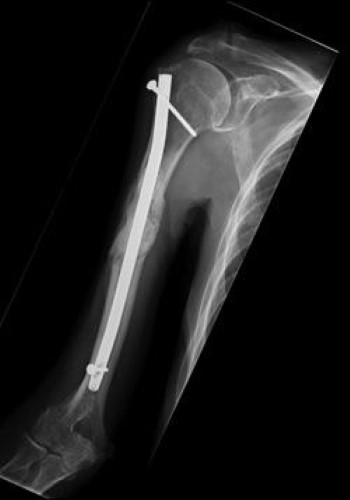

intramedullary rod in humerus

In this X-ray, the humerus has been stabilized with an intramedullary rod inserted down the center of the bone.

Reproduced from Schwartz HS, ed: Orthopaedic Knowledge Update: Musculoskeletal Tumors 2. Rosemont, IL, American Academy of Orthopaedic Surgeons, 2007, p 377.